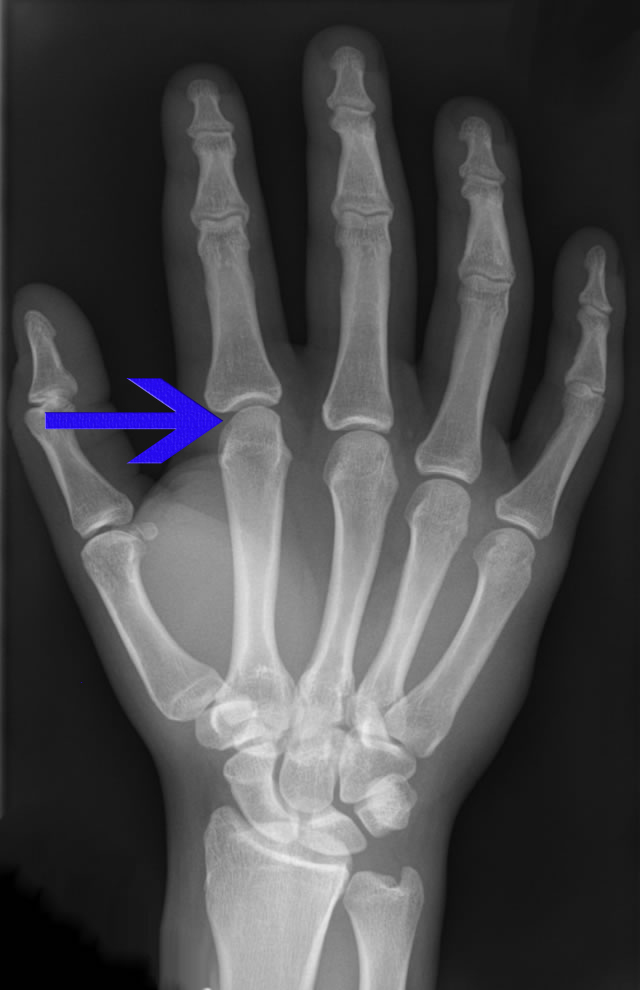

Metacarpophalangeal Joints (MCP) (MPJ)

- Metacarpal head is biconvex, cam-shaped so it extends further volarly than dorsally and is wider volarly than dorsally